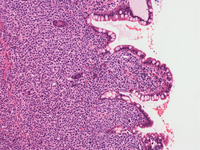

Small bowel biopsy

Small bowel resection shows an abnormal infiltration of discohesive cells with mucosal ulceration and granulation tissue. The cells are medium sized with occasional multinucleated giant cells. The background contains occasional eosinophils and neutrophils. By immunohistochemistry, the lesional cells show patchy weak CD45 staining and diffuse strong CD117 staining (shown here).